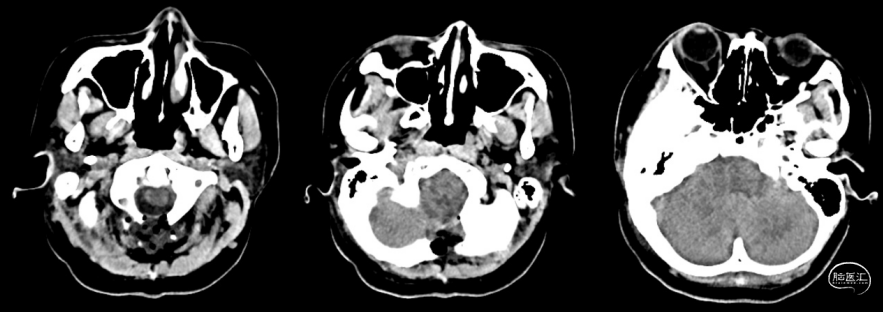

图3. 术后2天复查头颅CT:后颅窝减压术后改变。部分枕骨、C1后弓磨除。

术后6天患者下地活动后出现呕吐一次,持续头痛,头痛在坐起时加剧,平卧后缓解。术后7天予腰穿,脑脊液压力大于330mmH₂O,淡黄澄清,脑脊液常规及生化:隐血试验阳性、有核细胞22×10^6/L↑、红细胞96×10^6/L↑、潘氏试验阳性↑、中性粒细胞15%↑、淋巴细胞81%↑、单核细胞4%↓、蛋白含量67.8mg/dL↑。患者诉腰穿后头痛短暂缓解。术后8天再次腰穿压力为180mmH₂O。期间予甘露醇、甘油果糖降颅压治疗,但患者头痛症状无改善。复查头颅CT示后颅窝硬膜外血肿(术区外)(图4)。术后9天,患者出现胸闷、头晕、头痛、呼吸深快,予对症治疗。复查头颅CT示硬膜外血肿较前略吸收,多发脑池变窄,脑室变小(图5)。术后10天,患者突发癫痫大发作,予力月西镇静。病情稳定后复查头颅CT示硬膜外血肿较前大致相仿(图6)。